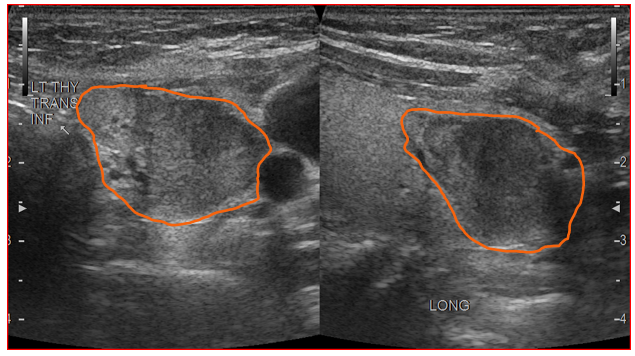

ID this artifact

edge shadow

comet tail

This artifact is?

mirror image